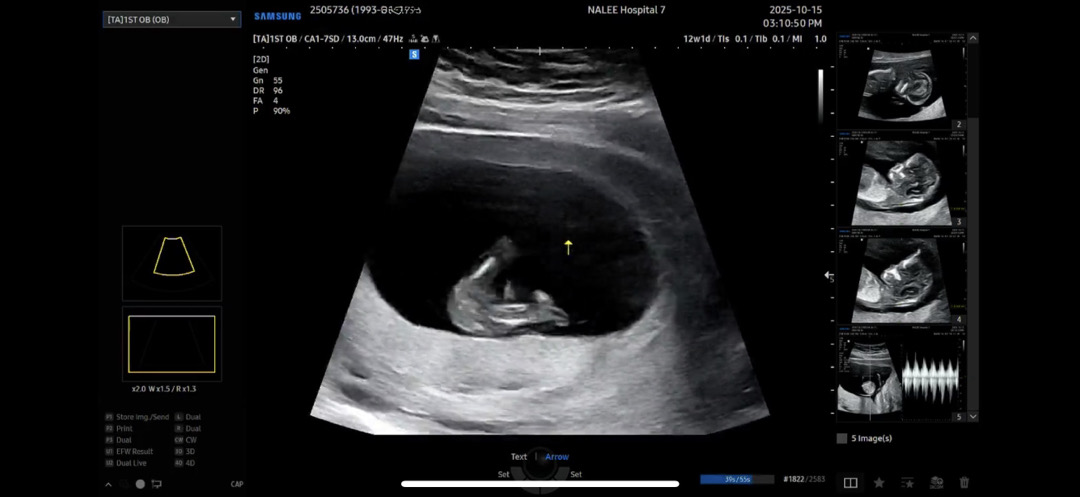

12주 성별 투표해주세요🫶🏻

의사선생님께서 높은 확률로 성별 추측해주셨는데 막삭 다시 영상 돌려보니 뚜렷하게 보이질 않아서 몇개 캡쳐해봤어요!!